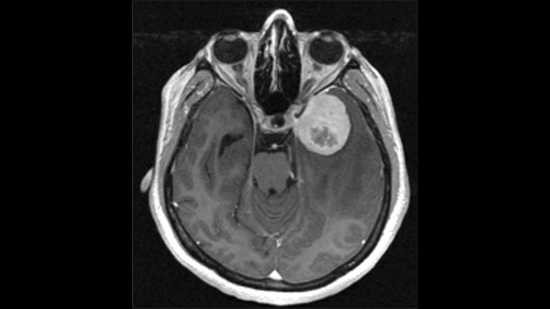

New genetic biomarker flags aggressive brain tumors

November 22 2025 – ROCHESTER, Minn. — Clinicians typically classify meningiomas — the most common type of brain tumor — into three grades, ranging from slow-growing to aggressive.

But a new multi-institutional study suggests that appearances may be deceiving. If a tumor shows activity in a gene called telomerase reverse transcriptase (TERT), it tends to recur more quickly, even if it looks low-grade under the microscope.

The findings, published in Lancet Oncology, could significantly change how doctors diagnose and treat meningiomas.

“High TERT expression is strongly linked to faster disease progression,” says Gelareh Zadeh, M.D., Ph.D., a neurosurgeon at Mayo Clinic and senior author of the study. “This makes it a promising new biomarker for identifying patients who may be at greater risk of developing aggressive disease.”